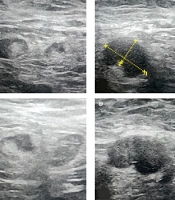

Based on the findings, having more than three ipsilateral lymph nodes with a cortical thickness of ≥ 3 mm showed 94.3% specificity for diagnosing axillary lymph node involvement. Among our patients, 49 (20.5%) exhibited lymphadenopathy with a cortical thickness of ≥ 3 mm in ≥ 3 lymph nodes. According to these criteria, 129 (56%) patients had metastatic lymphadenopathy with a sensitivity of 64.6% and a specificity of 91.4% and did not benefit from SLNB. Figures 2 - 4 demonstrate several ultrasound features of metastatic axillary lymph nodes and primary tumors.

Ultrasound Features of metastatic axillary lymph nodes: A, US image shows a metastatic axillary node with a focally eccentric thickened cortex (arrow); B, US image shows a 16 mm metastatic axillary node with an abnormal round shape, partial loss of the fatty hilum, and a 9 mm thickened cortex (calipers2); C, US image shows another infiltrated lymph node with an abnormal focal bulge in the cortex; D, Another biopsy-proven metastatic lymph node in a 63-year-old female patient with invasive ductal carcinoma (IDC). Ultrasound image shows an oval-shaped, marked hypoechoic and enlarged lymph node with absent fatty hilum.